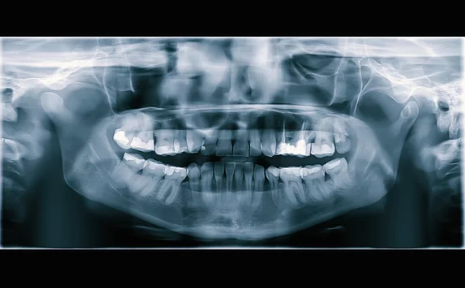

1. カウンセリング・精密検査(CT撮影など)

3. インプラント埋入手術

まずは検査を行い、適応かどうかを判断します。